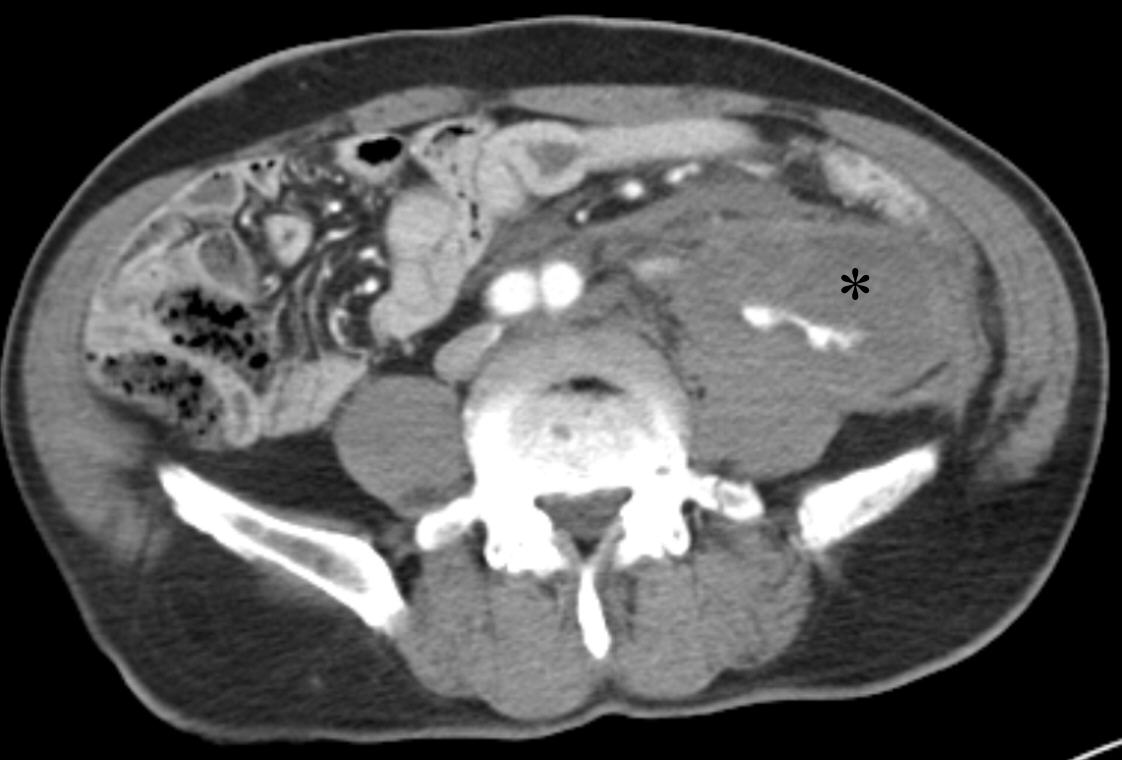

- Original Article Mar 30, 2026 Impact of embolic agents on outcomes of renal angiomyolipoma embolization: a dual-center retrospective cohort study Kun Yung Kim, Minuk Kim, Chang Jin Yoon, et al. Korean J Interv Radiol 2026;31(1):36-42.